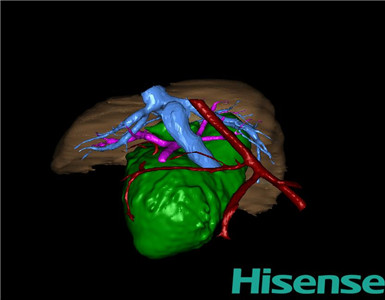

术前三维重建及手术方案设计:

将0.625mm双源薄层CT资料的静脉期和动脉期Dicom格式文件导入海信CAS系统。

通过调节窗宽窗位调整CT序号,对肝实质,胆囊,胆总管,下腔静脉,肝动脉、门静脉及肝静脉等进行三维重建;系统自动计算肝脏体积。

术前手术方案的规划。

完善术前准备后,选择右上腹纵口进入腹腔。结合海信CAS术前规划方案,探查见:胆总管4×2×2cm大小,胆囊约6×3×3cm,胆囊管迂曲,长约3cm。剥离、切除胆囊,游离胆总管,将之横断:①近端即肝总管,剪裁后备吻合用;②远端游离切除囊肿内壁,直至胆总管开口于十二指肠处,冲洗后予以结扎缝扎。距treits韧带20cm处直线切割吻合器横断空肠:①近端与其远端25cm处的空肠侧壁行端侧双层吻合,吻合口通畅;②远端断端封闭,其侧壁剪开,并经横结肠后提至肝门处,与剪裁的肝总管行端侧双层吻合。缝合修补胆囊床及系膜裂孔,肝门部放置橡胶引流管一根。温盐水冲洗腹腔。检查无活动性出血,清点纱布器械无误,依次缝合腹壁各层。术后胆囊标本家属过目,送检病理。手术时手术者可开启Hisense CAS系统手势控制功能,对胆囊周围血管、组织的解剖结构进行实时、全方观察、评估,起到术中导航作用。

术前三维重建:

重建图片